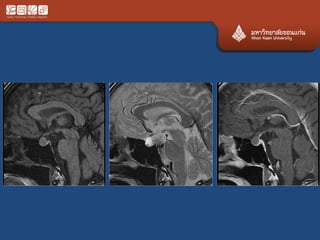

• #Craniopharyngioma

– Ddx dermoid (less likely)

• Bimodal distribution 5-15, 40-60

• 2 types

– Adamantinomatous : child with cal

– papillary

• Benign but adhere tightly

• Suprasellar, intrasellar, 3rd vent, sphenoid sinus,

nasopharynx

• Cystic solid, calcified mixed